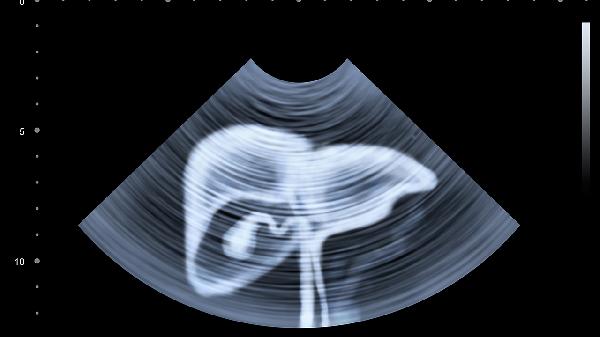

肝脏发出的这些求救信号,每一个都不容忽视。定期体检中的肝功能检查和肝脏超声,就像汽车的年检报告,能及时发现潜在问题。保持规律作息,控制体重,避免酒精伤害,都是在给这个沉默的劳模器官减轻负担。今天的观察清单,或许就是明天健康的保障。